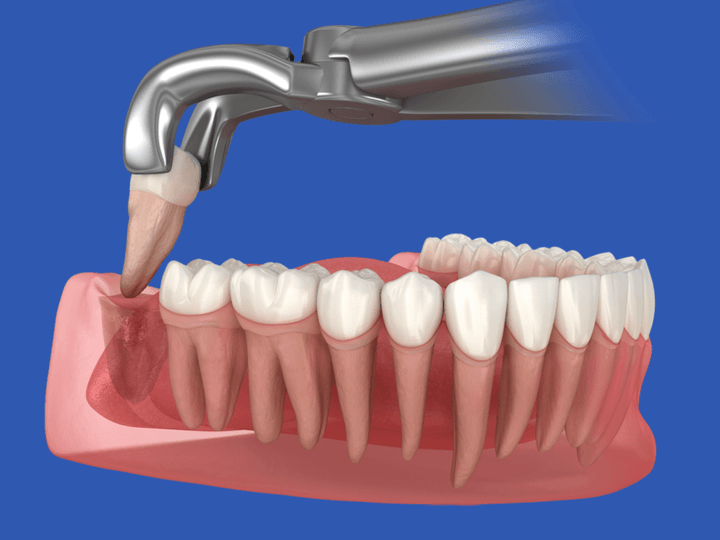

Екстракція ретинованих зубів – це складна хірургічна операція. Вилучення багатокореневого ретинованого зуба мудрості прирівнюють до операції з видалення апендикса. Найчастіше її проводять під місцевою анестезією, у непростих випадках – в медикаментозному сні. Її тривалість може становити близько 3 годин.